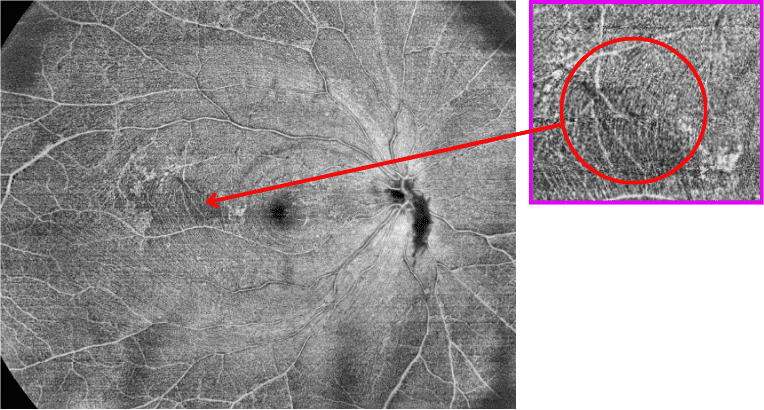

100kHz speed full-range swept-source OCT for anterior and posterior

- Full-Range wide-field Swept Source OCT

- 15mm x 15mm Wide-field OCTA

- Choroid OCTA with Quantification Parameters